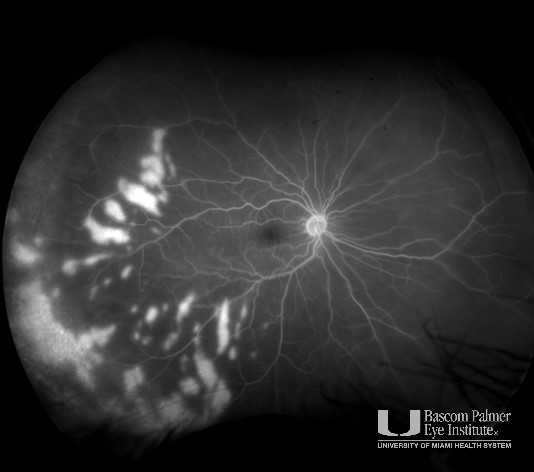

Pseudoangiomatous Retinal Gliosis

Specialty: Retina and Vitreous Diseases

Type: Ophthalmic Images

Include in Catalogue?: Yes

Original Contributor(s): Luis J. Haddock, MD; Marilyn A. Marquez, MD

Presenter/Faculty: Haddock, Marquez

Figure 1: Fundus photography of patient treated with Iodine plaque, PPV and endolaser due to Pseudoangiomatous retinal glisois that caused a retinal detachment. Figure 2: Bscan of same patient as figure 1 before surgery.